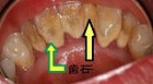

「歯周病」とは、細菌感染によって「歯を支えている顎の骨が溶かされてしまう病気」です

歯周病の初期は「痛い」「歯が動揺する」などの症状が出ないことが多いため、気づいた時にはすでに進行してしまっている場合が多いという特長があります。歯ぐきから出血する、口の中がネバネバする、口臭が気になる、などの症状に気づいたら、早めの診察を受けましょう。